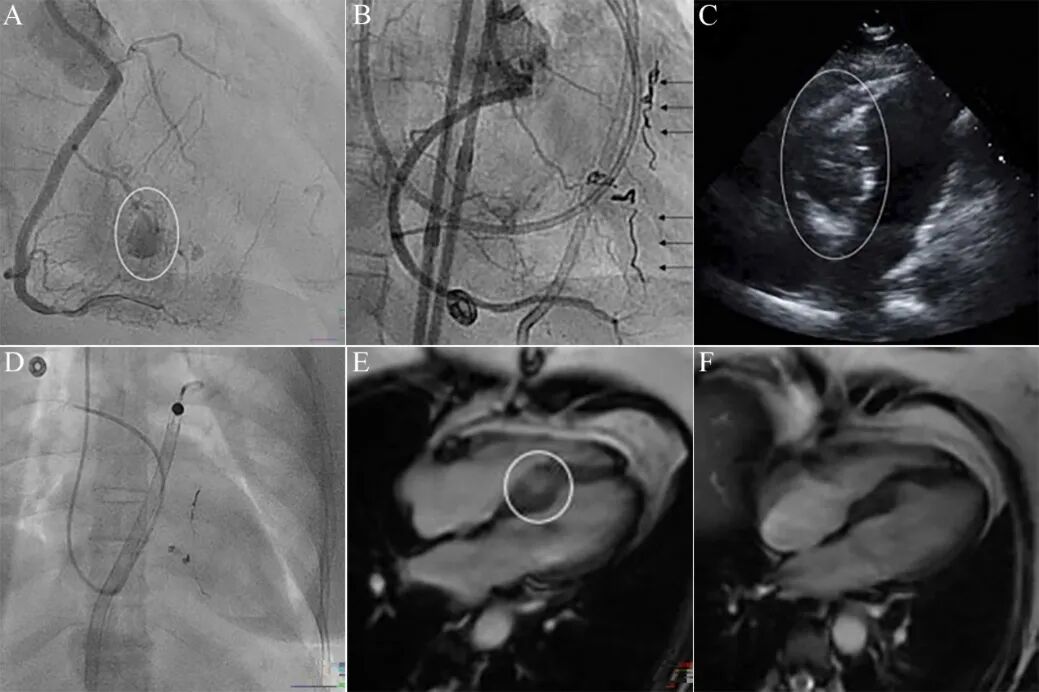

图9 室间隔血肿导致顽固性低血压[9]。

右冠CTO,经室间隔侧枝逆向开通后,造影发现穿隔支穿孔和室间隔血肿形成(A)。回病房后反复胸痛,血压稳定在100/78 mmHg左右,送回导管室复查造间隔血肿扩大,间隔侧枝弹簧圈封堵(B)。患者血压进行降低至70/48 mmHg,2小时内液体复苏3 L ,多巴胺和去甲肾上腺素静脉升压,效果不佳。超声显示室间隔血肿4.2cm,右室几乎被完全压闭(C),左室功能正常,心包积液微量。鉴于严重右心衰,经右股动脉植入右室辅助装置(Impella RP)(D),血流动力学立即恢复正常,血肿逐日缩小。出院前MRI(E)相比, 3个月后血肿基本吸收(F)。